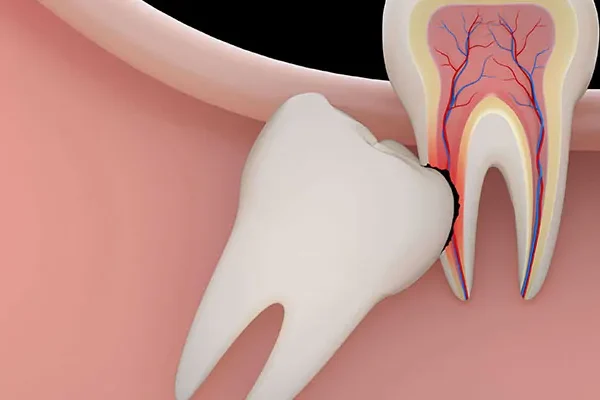

- Broken Tooth Treatment